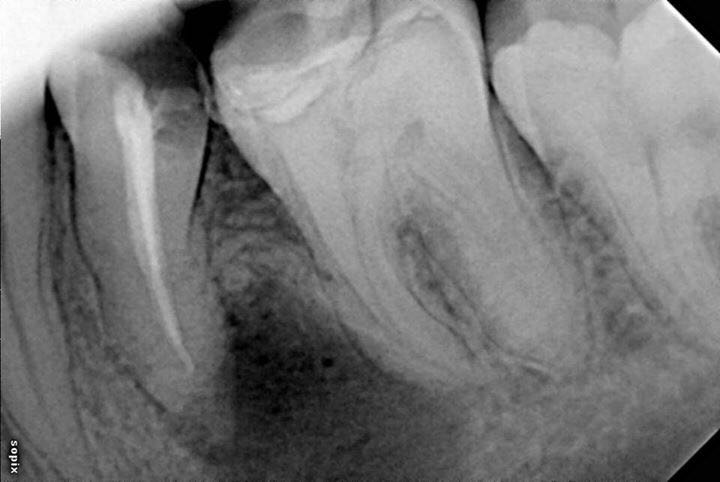

左下第二前磨牙根管再治疗

转自FB.根管再治疗,5个月随访,病变愈合良好。